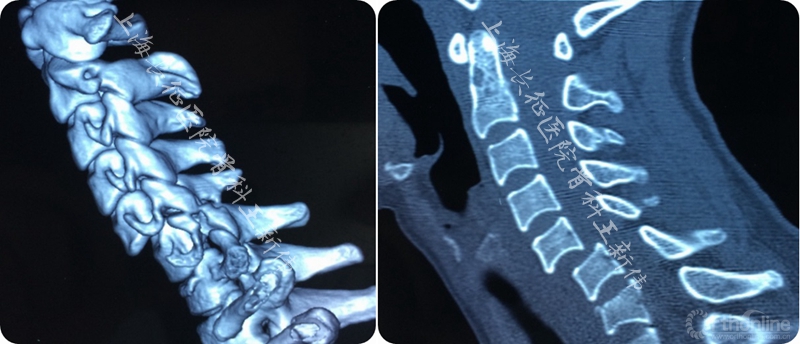

第一次术前颈椎CT三维重建

第一次术后颈椎CT三维重建,可见C6/7双侧仍存在关节绞锁

第二次术前颈椎MRI平扫,可见C6/7存在成角畸形,脊髓受压